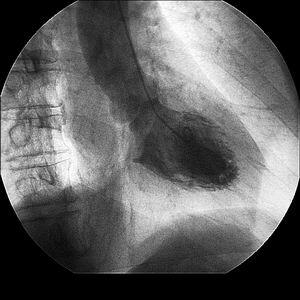

昨日の症例の画像を添付しましたので、ご参照ください。

RCA

DSA

いて、CAGは昨日と変化なし。ST levelもしばらくすると戻ってきました。DSA施行し

ましたが、腕頭動脈にも75%狭窄あり、RITAの造影も細く、蛇行が強い所見でした。